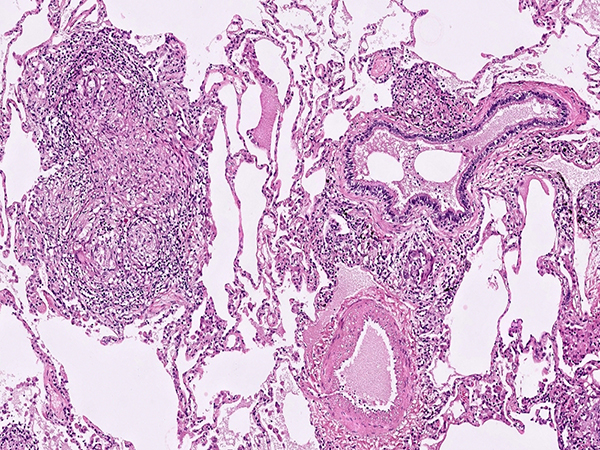

Clinical History:A 70 year-old male lifelong non-smoker presented to his pulmonologist with a 9 month history of progressive shortness of breath. The patient lives on a farm in rural New England where he gardens, hikes and clears trails, works with hay and horses, and uses a hot tub for muscle aches. Computed tomography scan demonstrated bilateral ground glass opacities with multiple small pulmonary nodules (Figure 1). Representative images from the right upper lobe wedge resections are shown (Figures 2-6).

Hot-Tub Lung (HTL) a relatively rare but important diagnostic consideration when faced with a diffuse pulmonary parenchymal granulomatous reaction in immunocompetent patients. HTL is caused by inhalation of water aerosol containing non-tuberculous mycobacteria (NTM), with most cases belonging to the Mycobacterium avium complex family. There is still debate as to whether HTL represents more of an infectious process or conversely a hypersensitivity reaction to the inhaled NTM organisms. This is mirrored by the histologic presentation that shares hybrid features of both an infectious granulomatous process as well as more traditional hypersensitivity pneumonitis (HP).

The most salient histologic finding is that of moderately well-formed largely non-necrotizing granulomas in a random, airspace, or bronchiolocentric distribution. The granulomas are generally larger and more well-formed than the “small poorly formed non-necrotizing granulomas” of HP. Necrosis is very rarely encountered in HTL (in contrast to infectious AFB or fungal infections). Exogenous or foreign polarizable materials within the granulomas, if present, would point to an aspiration pneumonitis, pneumoconiosis, or injection/talc granulomatosis depending on the findings. The granulomas of sarcoidosis tend to be ever larger and more well-formed with concentric fibrosis, and have a lymphangitic distribution (lymph node involvement plus pleural, septal, and peribronchovascular distribution). As with any interstitial lung disease, the proper clinical and radiologic context is extremely important in arriving at the correct diagnosis.